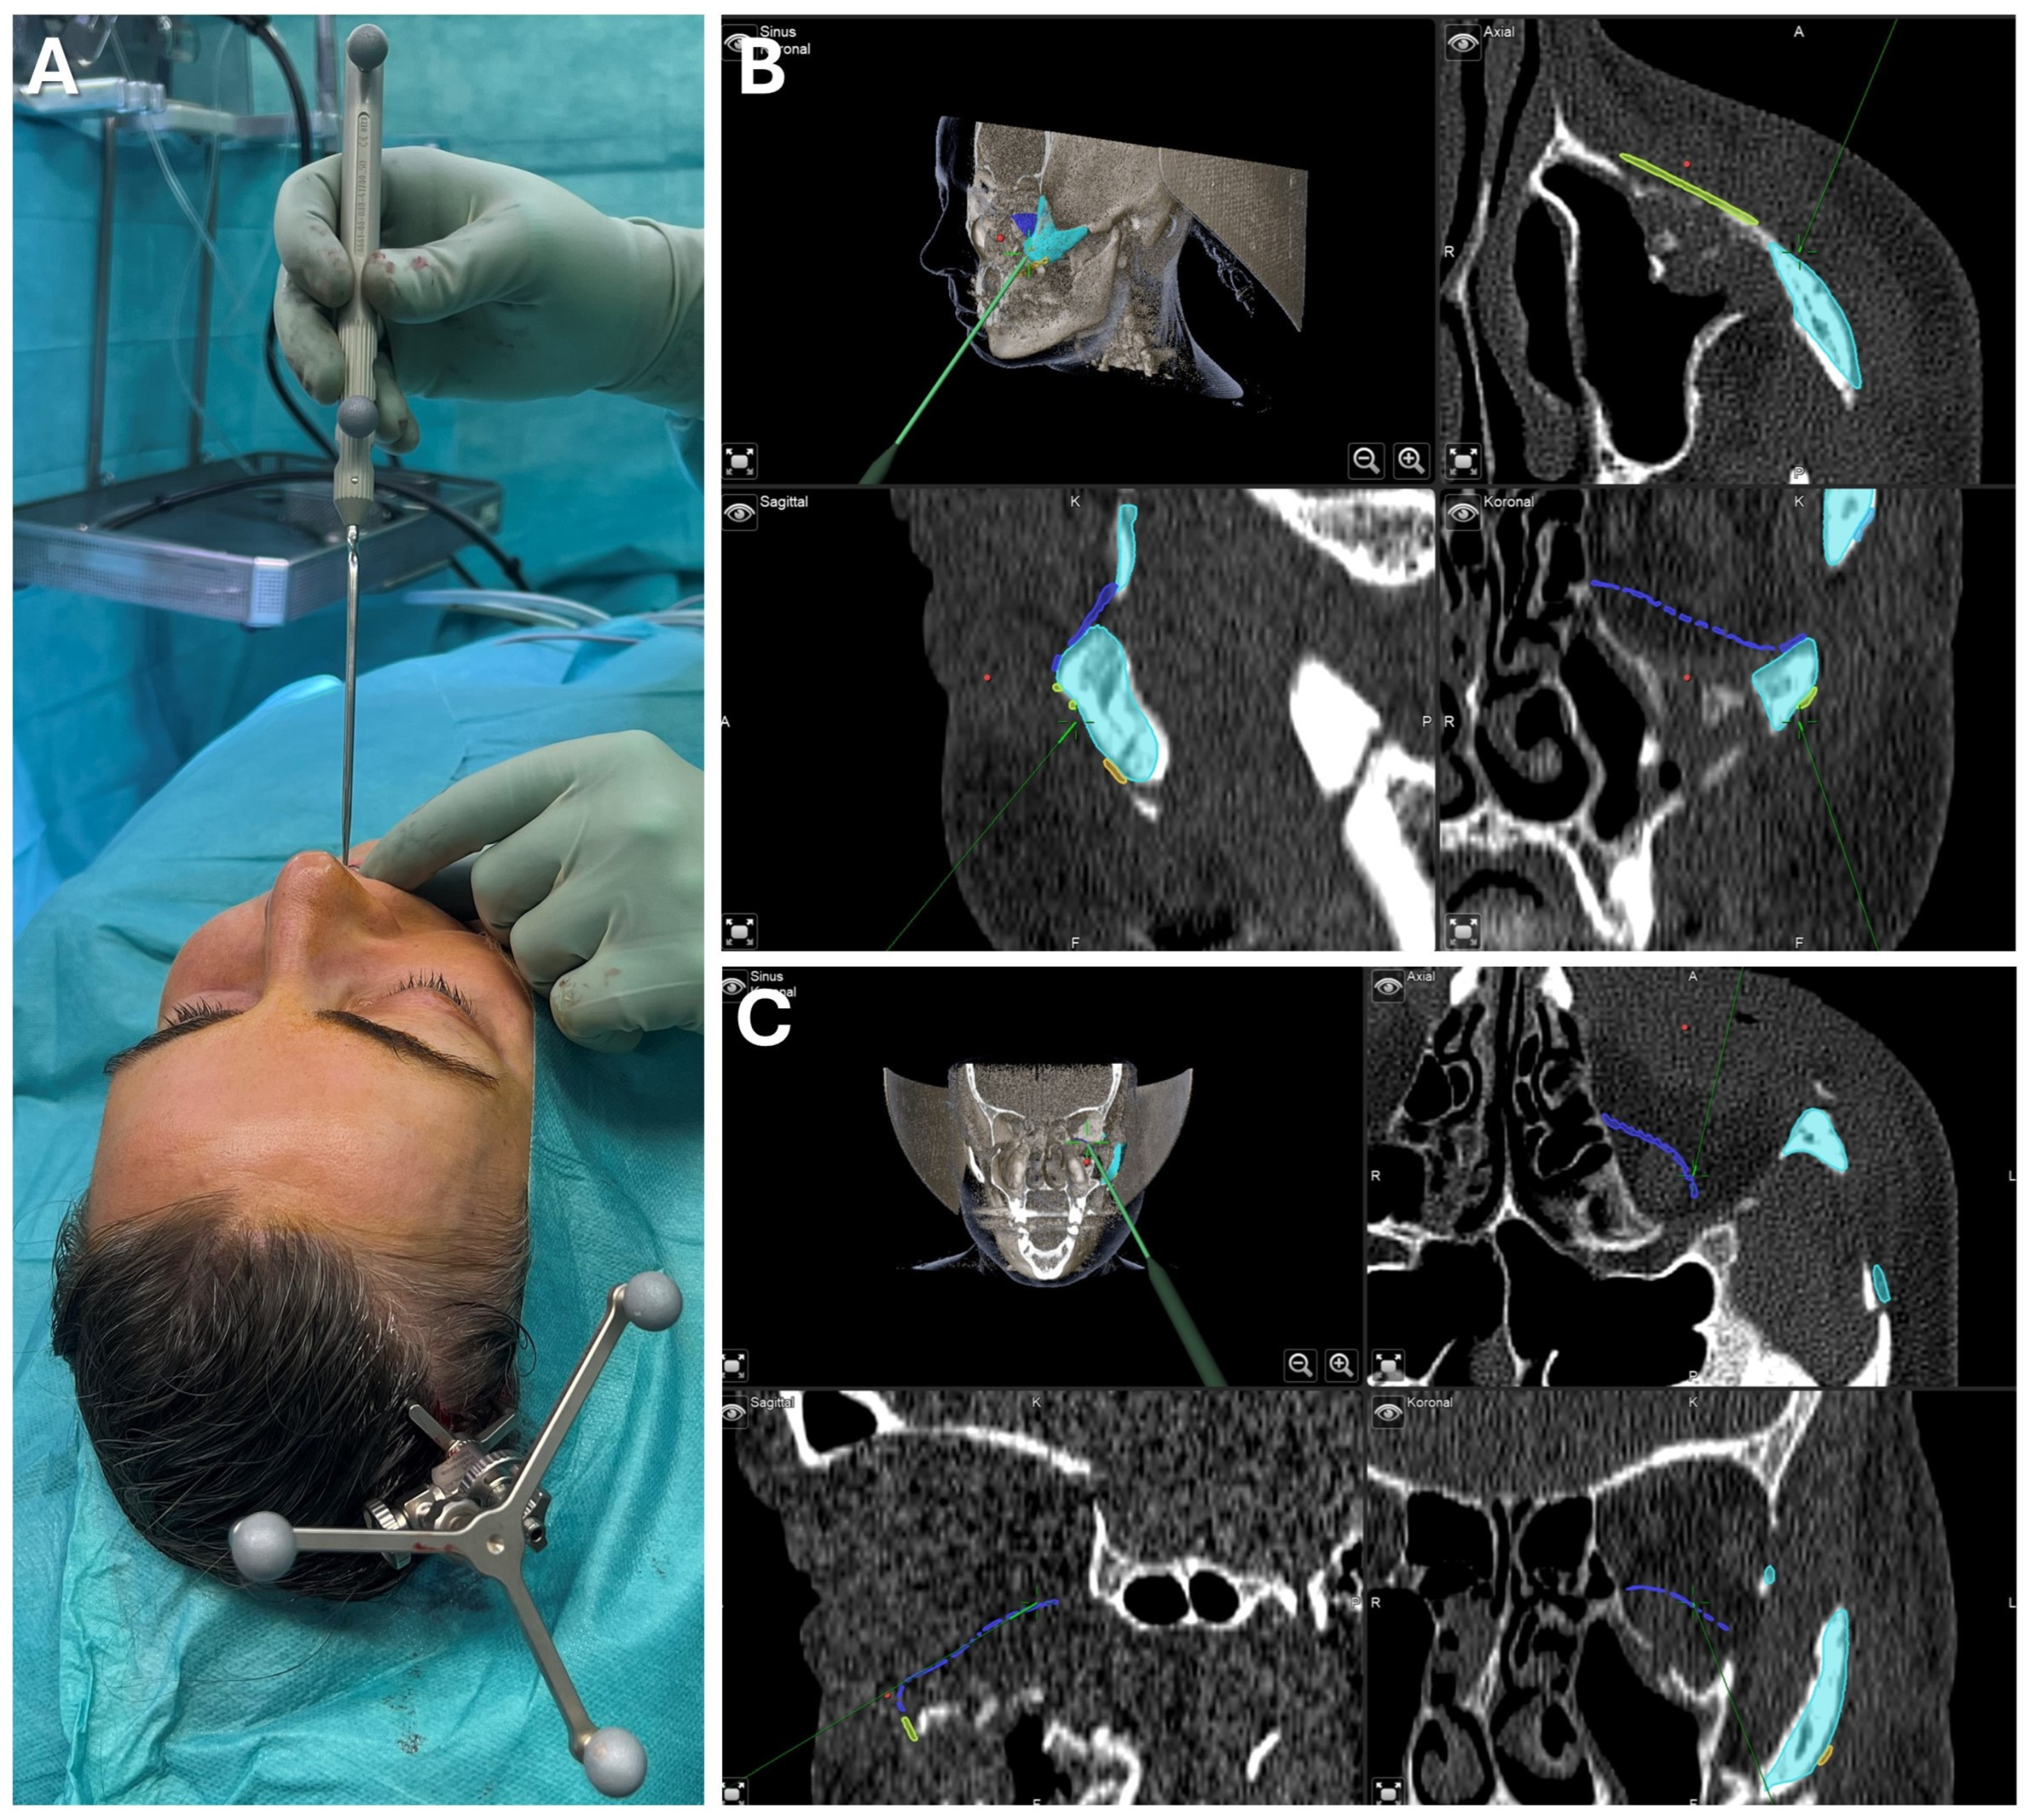

3.2.1. Case 1: Secondary Zygoma and Orbital Floor Repair Following Trauma